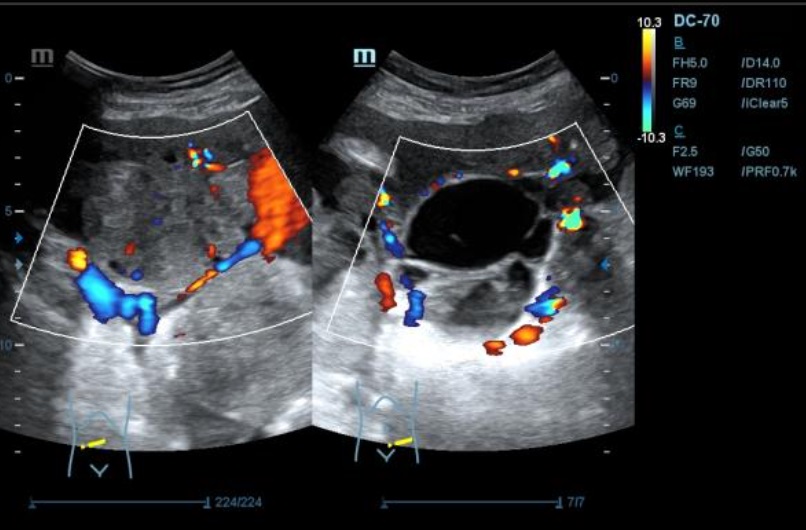

Ecografía: se observa presencia de líquido ascítico, e imagenes en hipomesogastrio hipo e hiper ecogénicas, tabicadas algunas, con efecto masa, con vascularizacion al Doppler que sugieren carcinoma de ovario.